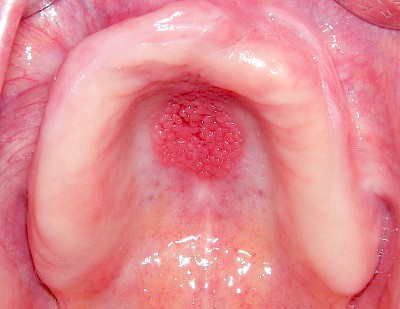

Schwellung ohne Eiter: kugelförmig

Demgegenüber entstehen Auftreibungen der Weichgewebe in Folge mechanischer Dauerreize (Reizfibrom) langsam über Wochen, Monate oder Jahre. Auch Gewohnheiten (Wangensaugen, Lippenbeißen) mit geringem Druck können als Dauerreiz in der Folge zu einer Wucherung der Weichgewebe führen. Fibrome werden nicht selten auch beobachtet in der Nähe einzelner fehlender Zähne – die Lippen oder Wangen beginnen dann, diesen Raum "aufzufüllen" (Vakatwucherung). Reizfibrome sind meist "kugelartig".